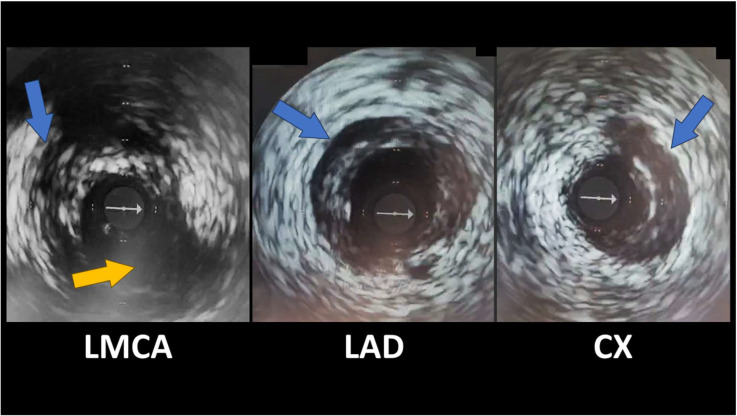

自发性冠状动脉剥离(SCAD)是急性冠状动脉综合征(ACS)的一种日益被认识的非动脉粥样硬化性原因,特别是在年轻女性中。这篇综述概述了SCAD独特的病理生理学,它与潜在的动脉病变如纤维肌肉发育不良有关,并强调了先进的血管内成像对准确诊断的关键作用。详细介绍了治疗的根本转变,有证据表明,由于血管自发愈合率高,稳定患者倾向于采用保守策略,为高风险病例保留技术上具有挑战性的侵入性干预措施。重要的是,本综述还涉及了长期结果,注意到复发率和主要不良心脏事件(MACE),持续胸痛的高患病率,以及β受体阻滞剂治疗在二级预防中的核心作用。最终,SCAD需要从标准的ACS协议转向个性化的方法,强调准确的诊断、谨慎的初始管理和警惕的长期随访。

Spontaneous coronary artery dissection (SCAD) is an increasingly recognized, non-atherosclerotic cause of acute coronary syndrome (ACS), particularly in younger women. This comprehensive review outlines SCAD's unique pathophysiology, which is linked to underlying arteriopathies like fibromuscular dysplasia, and highlights the critical role of advanced intravascular imaging for accurate diagnosis. A fundamental shift in management is detailed, with evidence favoring a conservative strategy for stable patients due to high rates of spontaneous vessel healing, reserving technically challenging invasive interventions for high-risk cases. Importantly, this review also addresses long-term outcomes, noting significant rates of recurrence and Major Adverse Cardiac Events (MACE), a high prevalence of persistent chest pain, and the central role of beta-blocker therapy in secondary prevention. Ultimately, SCAD requires a departure from standard ACS protocols towards a personalized approach that emphasizes accurate diagnosis, cautious initial management, and vigilant long-term follow-up.